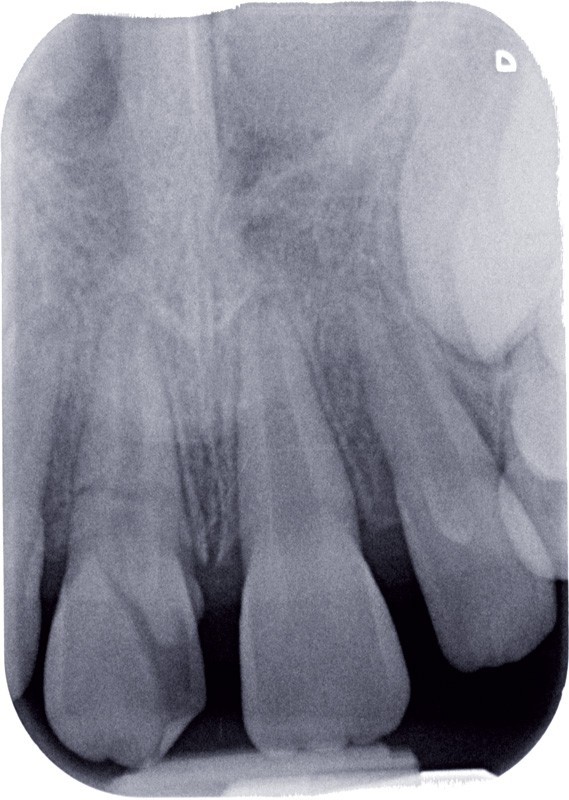

a à d Jeune patiente âgée de 8 ans, adressée suite à un traumatisme survenu 3 semaines auparavant, pour l’extraction de sa 21. La vue clinique montre un saignement ligamentaire, une mobilité coronaire et une fracture coronaire amélodentinaire longitudinale partant de l’angle mésial et se poursuivant en direction radiculaire sous-gingivale (a). Un test de vitalité positif indique que la dent est vitale, la radiographie permet de poser le diagnostic de fracture coronoradiculaire, et d’objectiver l’immaturité radiculaire (stade 8 de Nolla) (b). Une contention est mise en place et la plaie dentinaire coronaire est scellée au mieux par collage afin de limiter le risque d’une complication infectieuse (c). A 15 jours la dent est vivante et aucune complication n’est apparue (d). La patiente est revue après 3 mois pour déposer la contention, le test de vitalité est positif, et la radiographie de contrôle montre une apexogenèse en cours (e). Cependant la gencive s’est invaginée dans le trait de fracture (f). La zone est débridée sous microscope (g) puis scellée et reconstituée à l’aide d’un adhésif SAM et d’un composite fluide (h). Le contrôle radiographique à 6 mois est satisfaisant (i). Ce cas clinique illustre le fort potentiel des pulpes jeunes et du ligament alvéolodentaire à résister aux agressions et à assurer les fonctions dentinogénétiques et l’édification radiculaire.